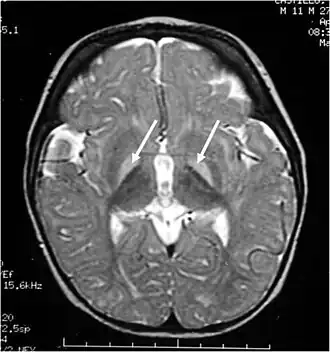

MRI van de hersenen. Hyperintense laesies van de basale kernen op T2-gewogen afbeeldingen. | ||||

Kernicterus[1] is een zeldzame aandoening waarbij de hersenen worden beschadigd als gevolg van een te hoog bilirubinegehalte in het bloed van baby's. Het woord kern in kernicterus verwijst naar de basale kernen in de hersenen. Deze kern speelt een belangrijke rol in het bewegen en het reageren op emoties. Een Engelse term die hiervoor gebruikt wordt is Bilirubin-Induced Neurologic Dysfunction (BIND). Induced betekent veroorzaakt door, Neurologic Dysfunction betekent dat de hersenen niet meer goed kunnen functioneren.

Kernicterus wordt veroorzaakt door een te hoge hoeveelheid van het stofje bilirubine. Een te hoge hoeveelheid aan bilirubine is schadelijk voor de bepaalde diepgelegen delen van de hersenen. Een van de delen die gevoelig is voor beschadiging is de globus pallidus. De globus pallidus is betrokken bij het reguleren van vrijwillige bewegingen.